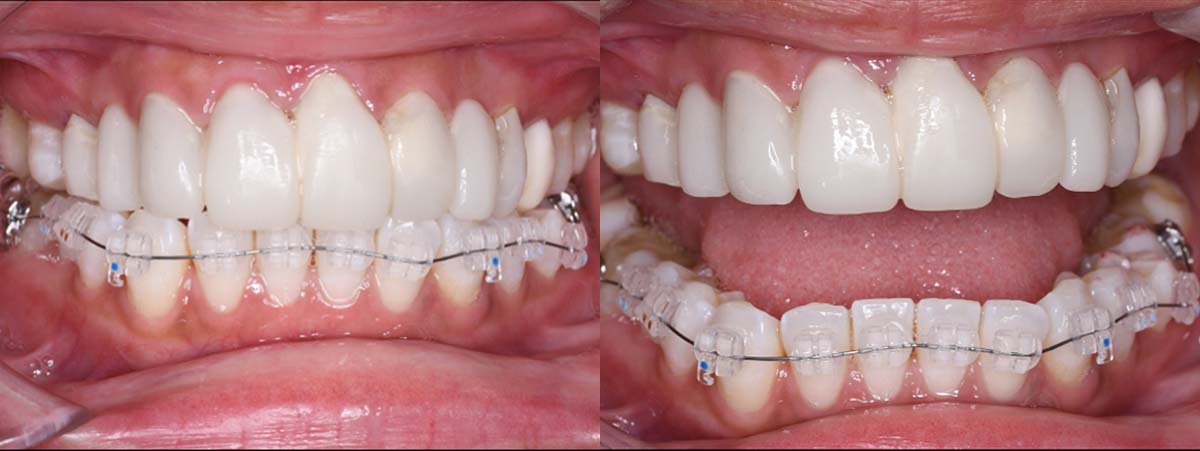

バイトアップ後

2024年 10月 下顎MTM開始